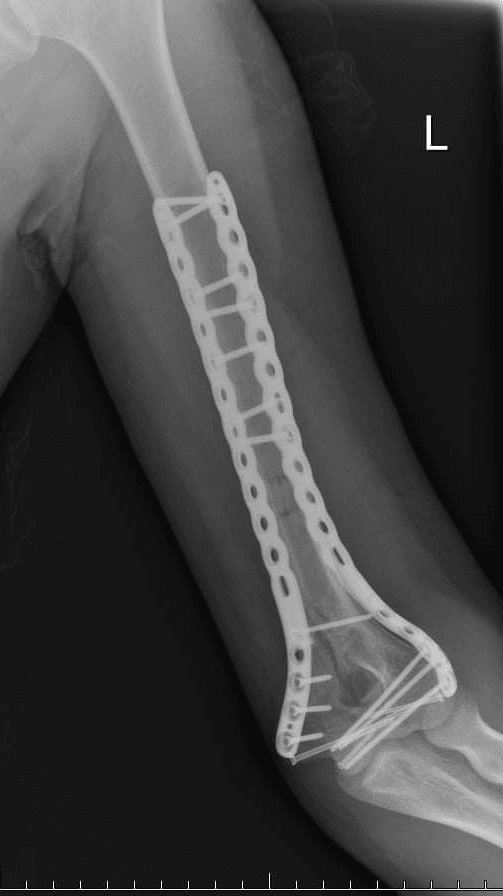

Due to its outstanding biocompatibility, tantalum is being studied and used in:

- Orthopedic implants

- Dental implants

- 3D-printed porous scaffolds for bone in-growth

- Novel alloys such as TNTZ (Titanium-Niobium-Tantalum-Zirconium alloys)

Its resistance to bodily fluids and promotion of bone adhesion makes it a strong candidate for long-term implants. However, AMAZEMET does not currently provide medical-grade tantalum but supports research institutions developing novel biomaterials based on tantalum and other metals.